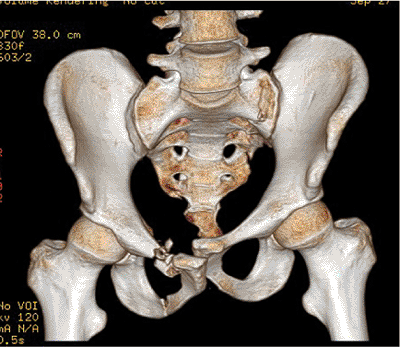

stable and balanced fixation (Fig. 39.5). Some

clinicians prefer three-dimensional CT scans to improve their

understanding of the fracture details and deformity patterns (Fig. 39.6).

Figure 39.6.

Three-dimensional CT scanning reveals the pelvic injury zones but not in sufficient detail to be used alone in planning. Just as when viewing two-dimensional CT images, the surgeon must know if the patient is wrapped in a pelvic circumferential sheet or other type of pelvic binder at the time of the CT scanning. |